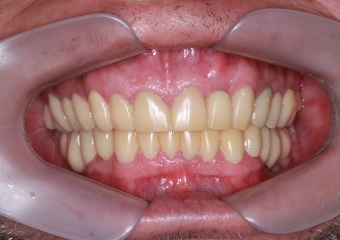

Imagem Próteses Definitivas em Setembro de 2016

Próteses Definitivas e Facetas em Porcelana, em Setembro de 2016

Sorriso Final, em 2016